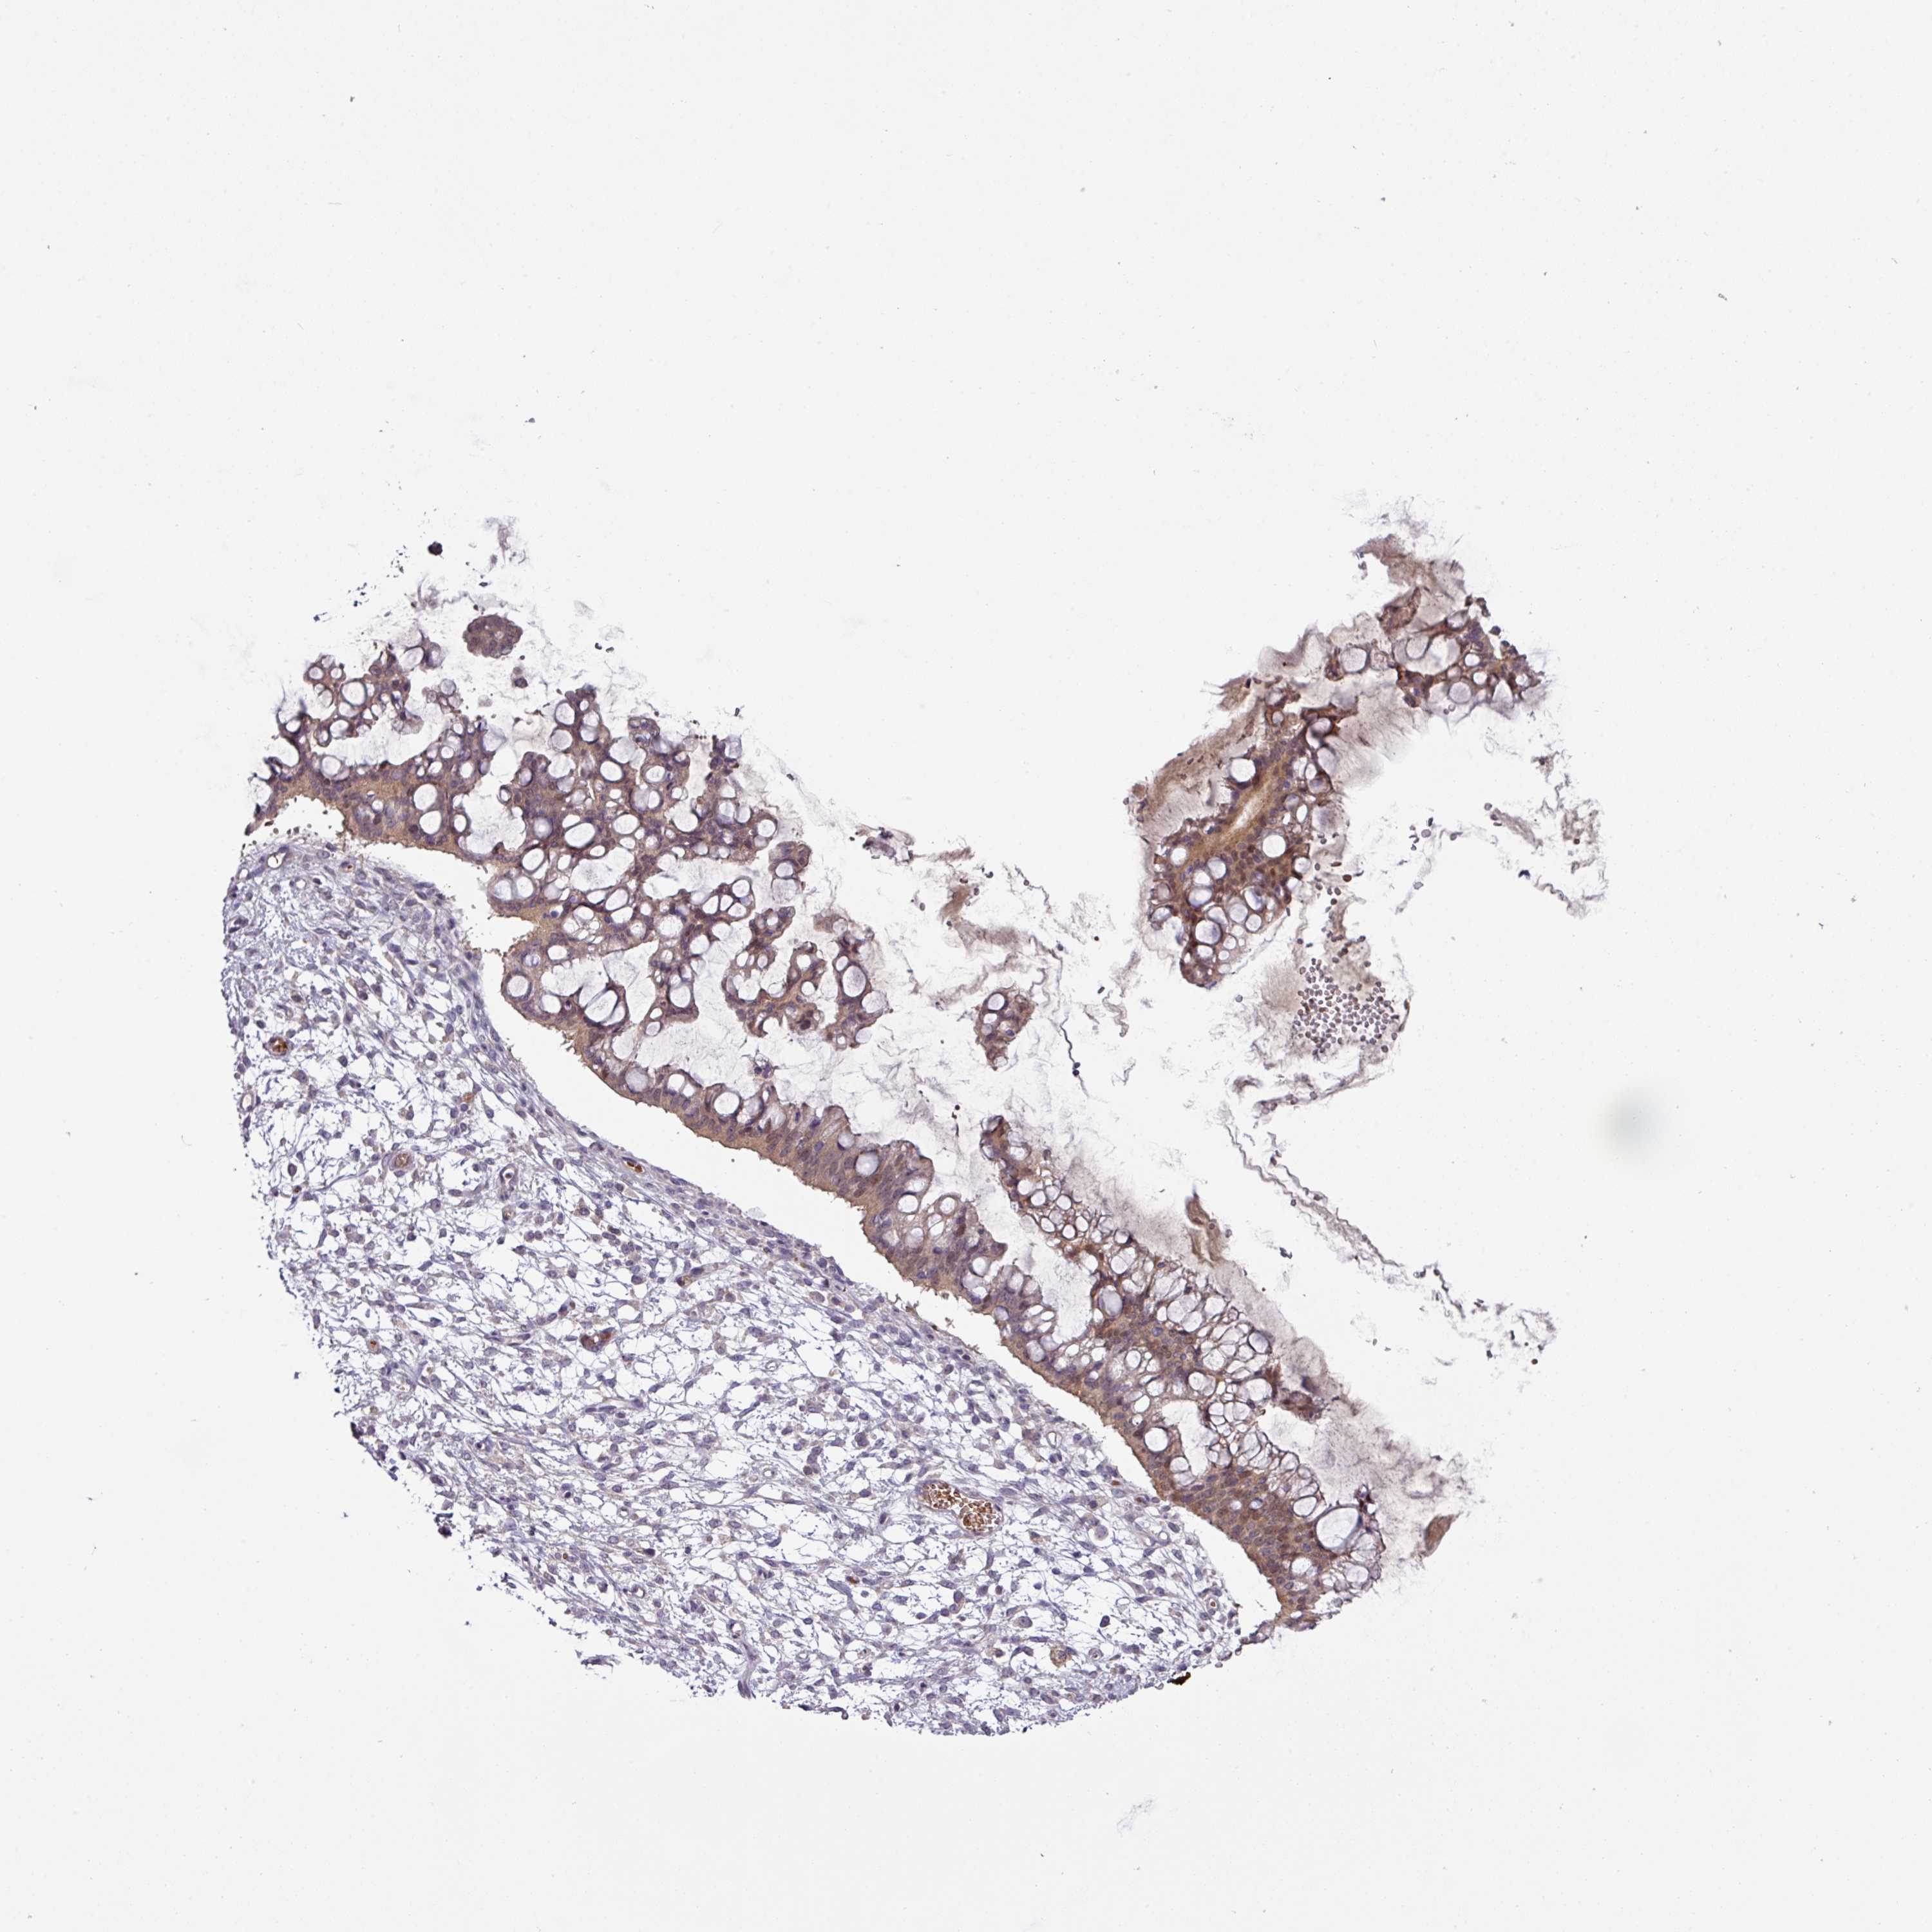

OVARIAN CANCER - Protein expressioni

A mouse-over function shows sample information and annotation data. Click on an image to view it in a full screen mode. Samples can be filtered based on level of antibody staining by selecting one or several of the following categories: high, medium, low and not detected. The assay and annotation is described here.

Note that samples used for immunohistochemistry by the Human Protein Atlas do not correspond to samples in the TCGA dataset.

Antibody stainingi

Antibody staining in the annotated cell types in the current human tissue is reported as not detected, low, medium, or high, based on conventional immunohistochemistry profiling in selected tissues. This score is based on the combination of the staining intensity and fraction of stained cells.

Each image is clickable and will lead to virtual microscopy that enables deeper exploration of all samples and also displays staining intensity scores, fraction scores and subcellular localization as well as patient and tissue information for each sample.

Antibody HPA052014

Staining

High

Medium

Low

Not detected

Intensity

Strong

Moderate

Weak

Negative

Quantity

>75%

75%-25%

<25%

None

Location

Nuclear

Cytoplasmic/membranous

Cytoplasmic/membranous,nuclear

Cystadenocarcinoma, serous, NOS

Carcinoma, NOS

Cystadenocarcinoma, mucinous, NOS

Carcinoma, endometroid